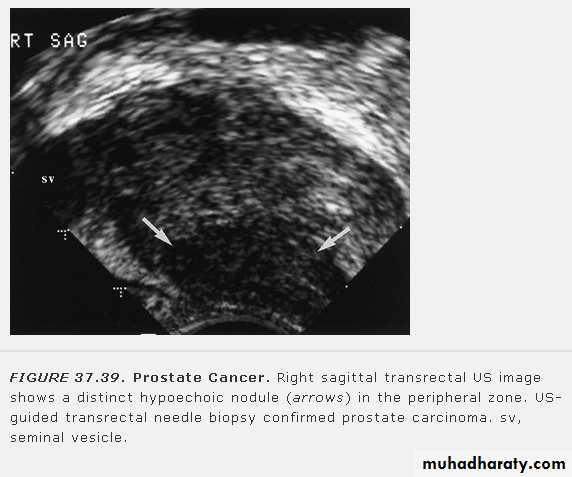

• Prostatic enlargement is very common in elderly men. It is usually due to benign prostatic hypertrophy but may be due to carcinoma.• TRUS: can show the overall size of the prostate and can diagnose relatively small masses within its substance. TRUS-guided biopsy is used for the diagnosis of prostatic carcinoma

• MRI: the zonal anatomy of prostate is very well demonstated by MRI. In T2 images, the peripheral zone(the most common origin of tumors) is of high signal intensity and the tumor is of low signal intensity. MRI is used to assess early stage prostatic cancer in patients being considered for radical surgery or radiotherapy. MRI is also used to demonstrate extracapsular tumor spread, to show invasion of the seminal vesicles, and to demonstrate possible LN metastases.